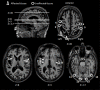

Optic ataxia is a neuropsychological disorder that affects the ability to interact with objects presented in the visual modality following either unilateral or bilateral lesions of the posterior parietal cortex (PPC). Patients with optic ataxia fail to reach accurately for objects, particularly when they are presented in peripheral vision. The present review will focus on a series of experiments performed on patient M.H. Following a lesion restricted largely to the left PPC, he developed mis-reaching behavior when using his contralesional right arm for movements directed toward the contralesional (right) visual half-field. Given the clear-cut specificity of this patient's deficit, whereby reaching actions are essentially spared when executed toward his ipsilateral space or when using his left arm, M.H. provides a valuable "experiment of nature" for investigating the role of the PPC in performing different visually guided actions. In order to address this, we used kinematic measurement techniques to investigate M.H.'s reaching and grasping behavior in various tasks. Our experiments support the idea that optic ataxia is highly function-specific: it affects a specific sub-category of visually guided actions (reaching but not grasping), regardless of their specific end goal (both reaching toward an object and reaching to avoid an obstacle); and finally, is independent of the limb used to perform the action (whether the arm or the leg). Critically, these results are congruent with recent functional MRI experiments in neurologically intact subjects which suggest that the PPC is organized in a function-specific, rather than effector-specific, manner with different sub-portions of its mantle devoted to guiding actions according to their specific end-goal (reaching, grasping, or looking), rather than according to the effector used to perform them (leg, arm, hand, or eyes).